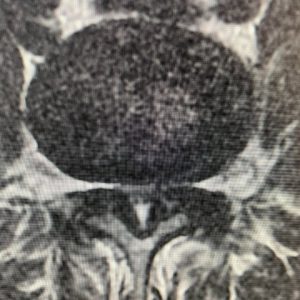

The patient in the images had mostly back pain that was worse with standing for 5 minutes associated with her L4-5 instability. Therefore, she was best served with a laminectomy and fusion surgery. Don’t settle for a one-size-fits-all approach to surgery. Talk to your surgeon about all the options, and if you don’t understand completely, seek out a second opinion.